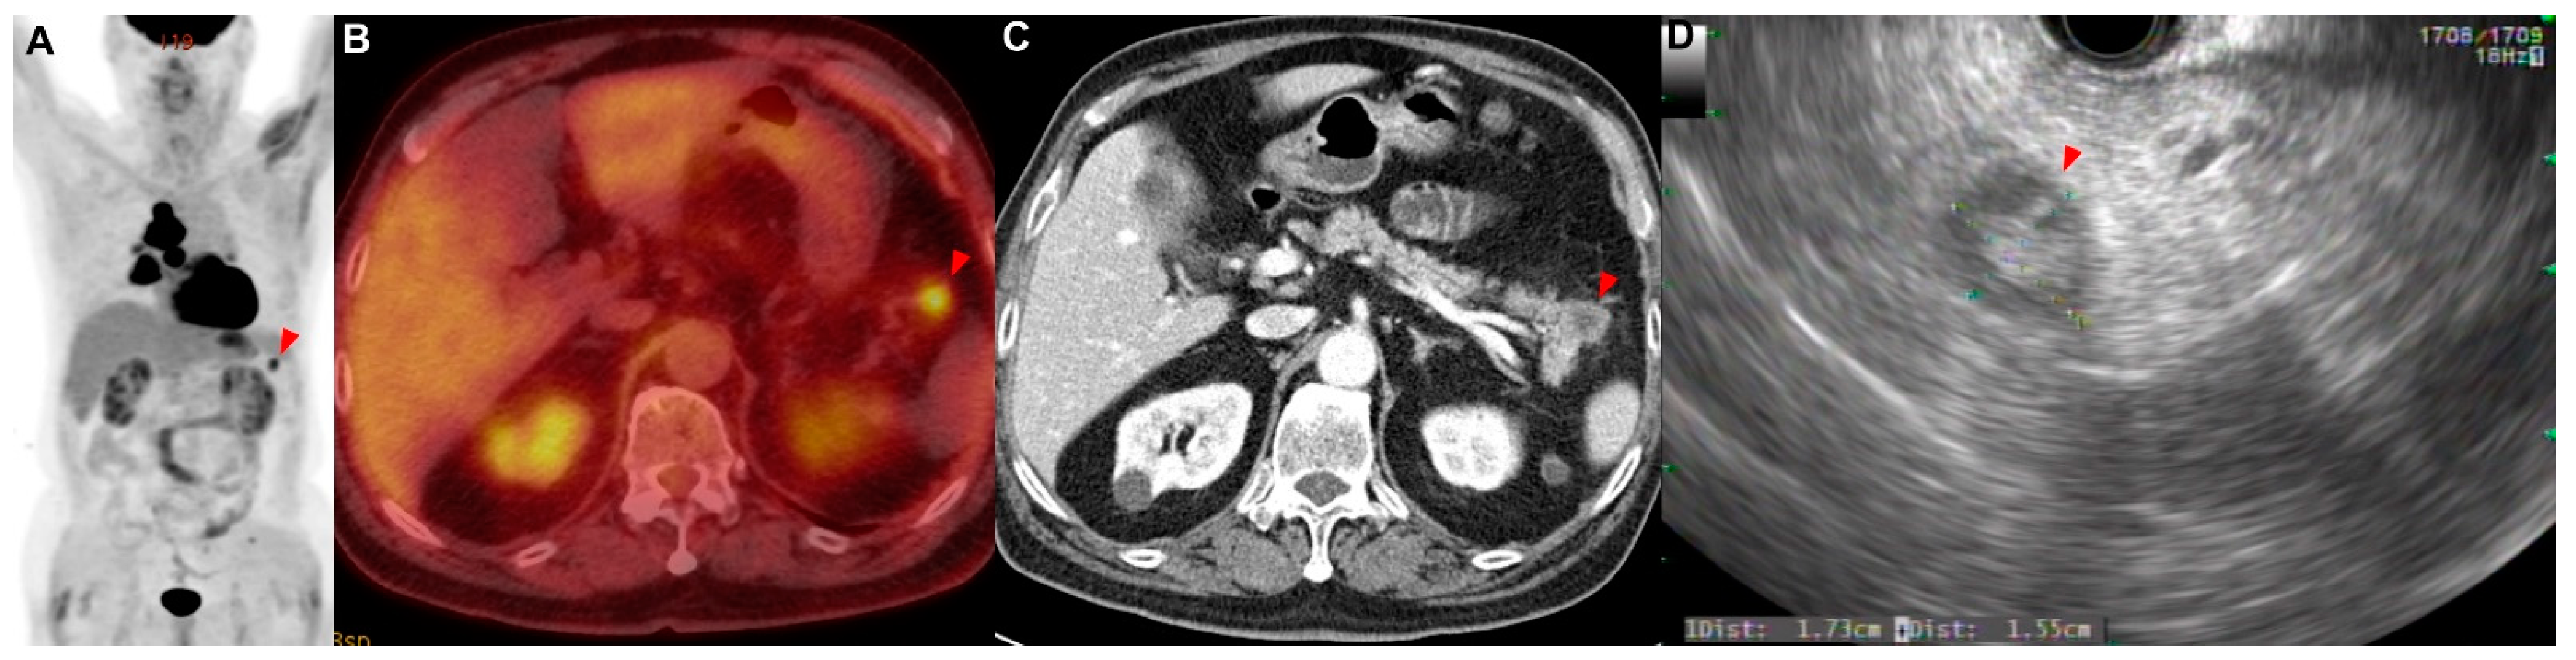

A 79-year-old woman who had never smoked presented with 2 weeks of hoarseness and a history of hypertension and diabetes mellitus. She stated that she had no other illnesses, including cardiovascular, allergic, rheumatic or respiratory conditions. A contrast-enhanced CT scan of her chest showed that a lung mass originating in the left upper lobe had invaded the mediastinum. No endobronchial tumor was observed on the bronchoscopy, and a narrowing of the apicoposterior segmental bronchus of the left upper lobe was observed. Adenocarcinoma was confirmed by brushing cytology of the apicoposterior segmental bronchus of the left upper lobe. If there was no metastasis, the tumor was considered stage IIIB as T4N2. On the PET/CT scan, hypermetabolic lesions were observed in the subcutaneous layer of the middle part of the right back (SUVmax = 4.64) and in the left breast (SUVmax = 3.52) (Figure 3A–C). A core-needle biopsy was performed on the lesion in the left breast (Figure 3D), and the pathological examination reported metastasis of lung adenocarcinoma (TTF-1: positive; GATA-3: negative) (Figure A1C,D). In addition, an excision biopsy was performed on the lesion of the right back, and the pathological examination showed metastasis of the lung adenocarcinoma (TTF-1: positive; ALK: negative; GATA-3: negative; CDX-2: negative) (Figure A1E,F). Additionally, EGFR 19 deletion mutation was detected in this metastatic tissue using an EGFR PCR test. Therefore, this patient was treated with an EGFR tyrosine kinase inhibitor for EGFR-mutated-stage-IV adenocarcinoma.

Figure 3. Patient 3: a 79-year-old woman diagnosed with lung adenocarcinoma with metastases in subcutaneous tissue. (AC) The PET/CT showed a metastatic lesion (red arrowhead) in the left breast. I PET/CT showed a metastatic lesion (white arrowhead) in the subcutaneous layer of the middle part of the right back. (D) The core needle biopsy was performed on the lesion of the left breast.